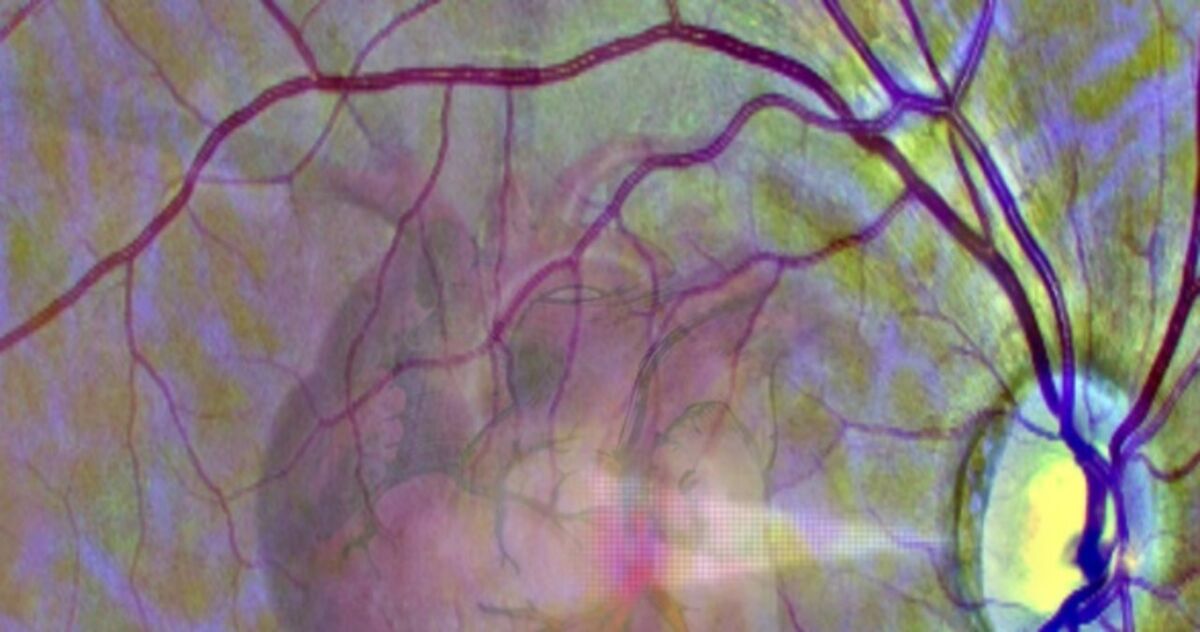

Mówimy często, że oczy są zwierciadłem duszy. Międzynarodowy zespół naukowców pod kierunkiem badaczy z University of Leeds twierdzą, że oczy mogą być też zwierciadłem serca. Na łamach czasopisma "Nature Machine Intelligence" informuje, że opracowany przez nich algorytm sztucznej inteligencji jest w stanie na podstawie obrazu siatkówki oka z 70-80 procentową dokładnością przewidzieć wysokie ryzyko ataku serca w następnym roku. W ten sposób, przy okazji wizyty u okulisty można dostać sugestię, by jak najszybciej wybrać się do kardiologa.